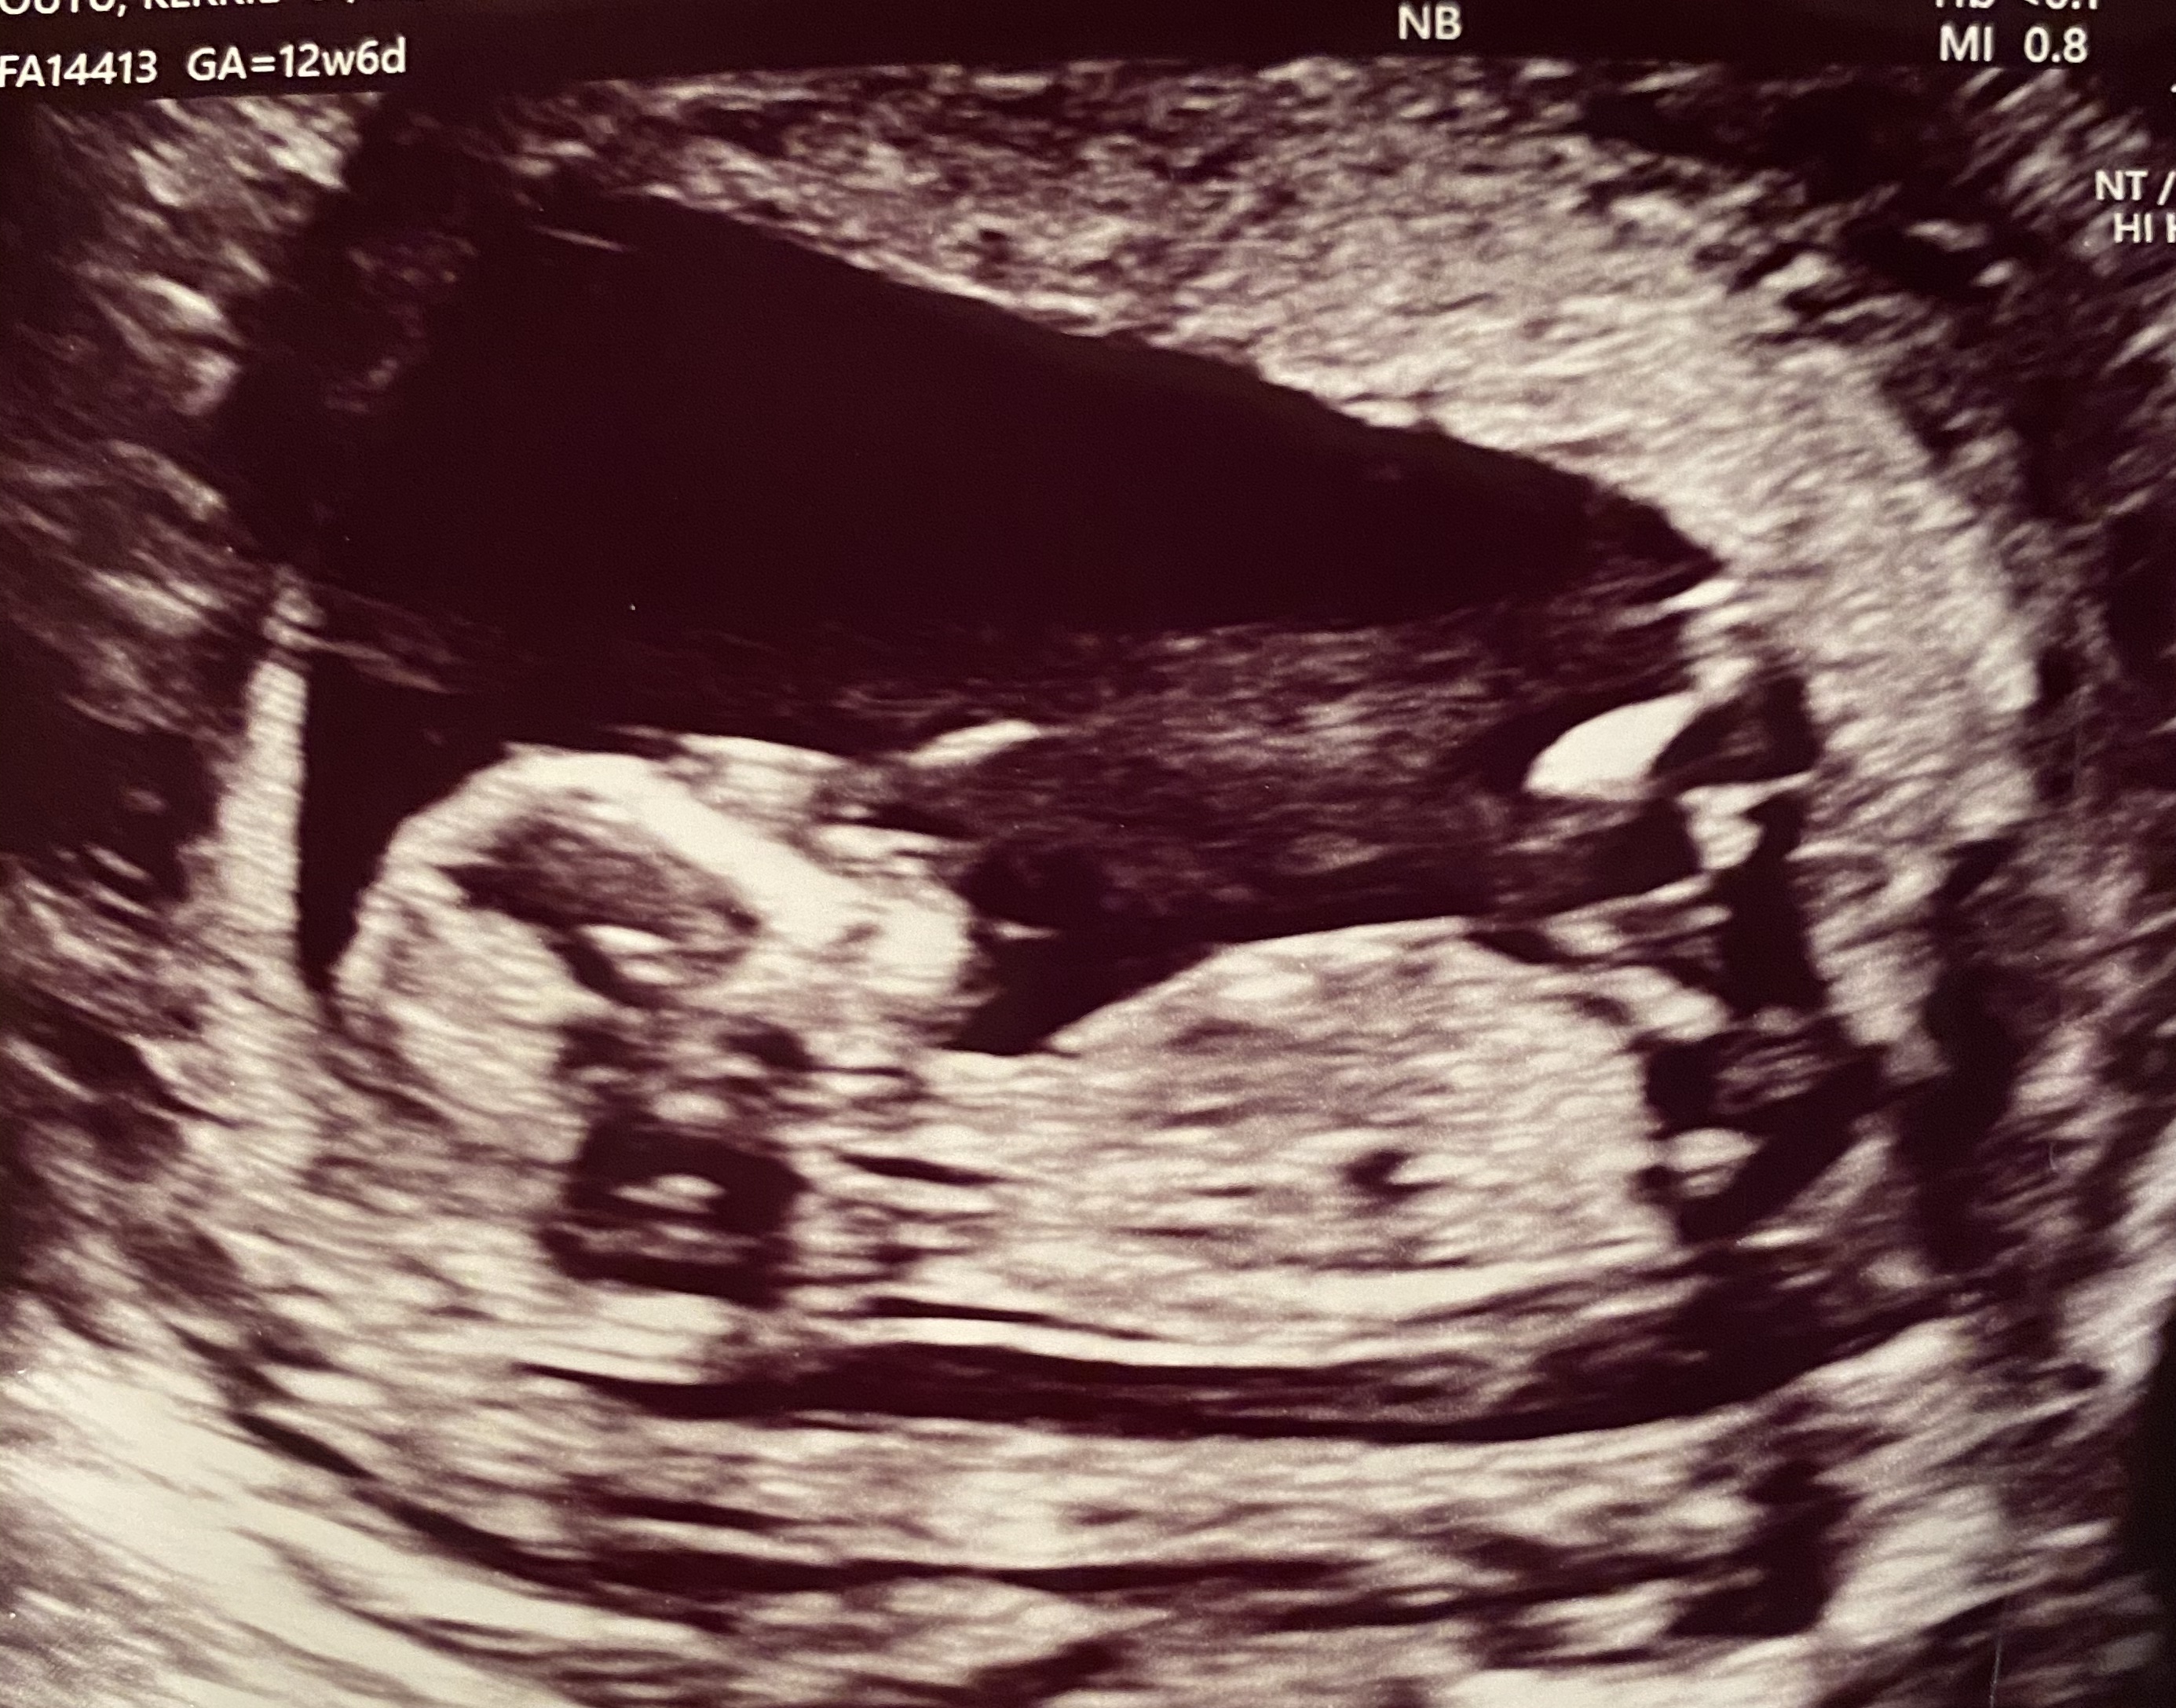

Hi! Can anyone please take a guess, boy or girl? I’ve been told this is a tricky one :think: but would love any guesses! I already have 2 boys so a girl would be special but another boy would be easier. However this baby in general looks different from my last and this pregnancy has been the complete opposite from my last so I’m optimistic this could be our girl but won’t hold my breath!

Attachment 42835